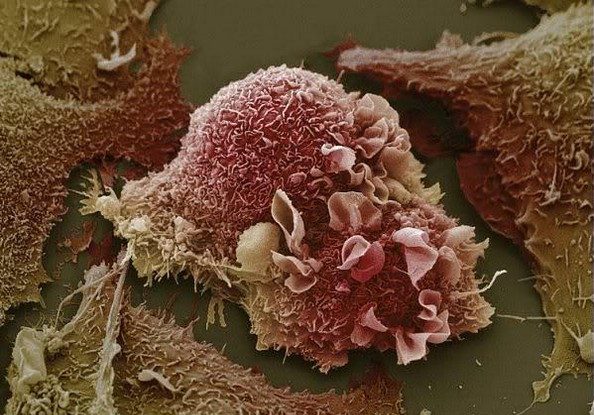

8. Бели дробови со рак